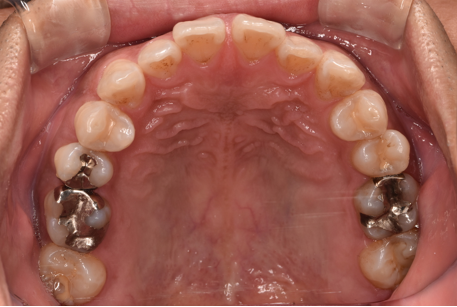

治療前

| カウンセリング・診断結果 | 診察したところ、上の前歯の真ん中に隙間が空いている状態でした(正中離開)。 |

| 行ったご提案・治療内容 | CTや3Dスキャンでの精密検査の結果、奥歯の噛み合わせ等には大きな問題はありませんでした。 そのため、インビザラインライトでの治療をご提案しました。 |